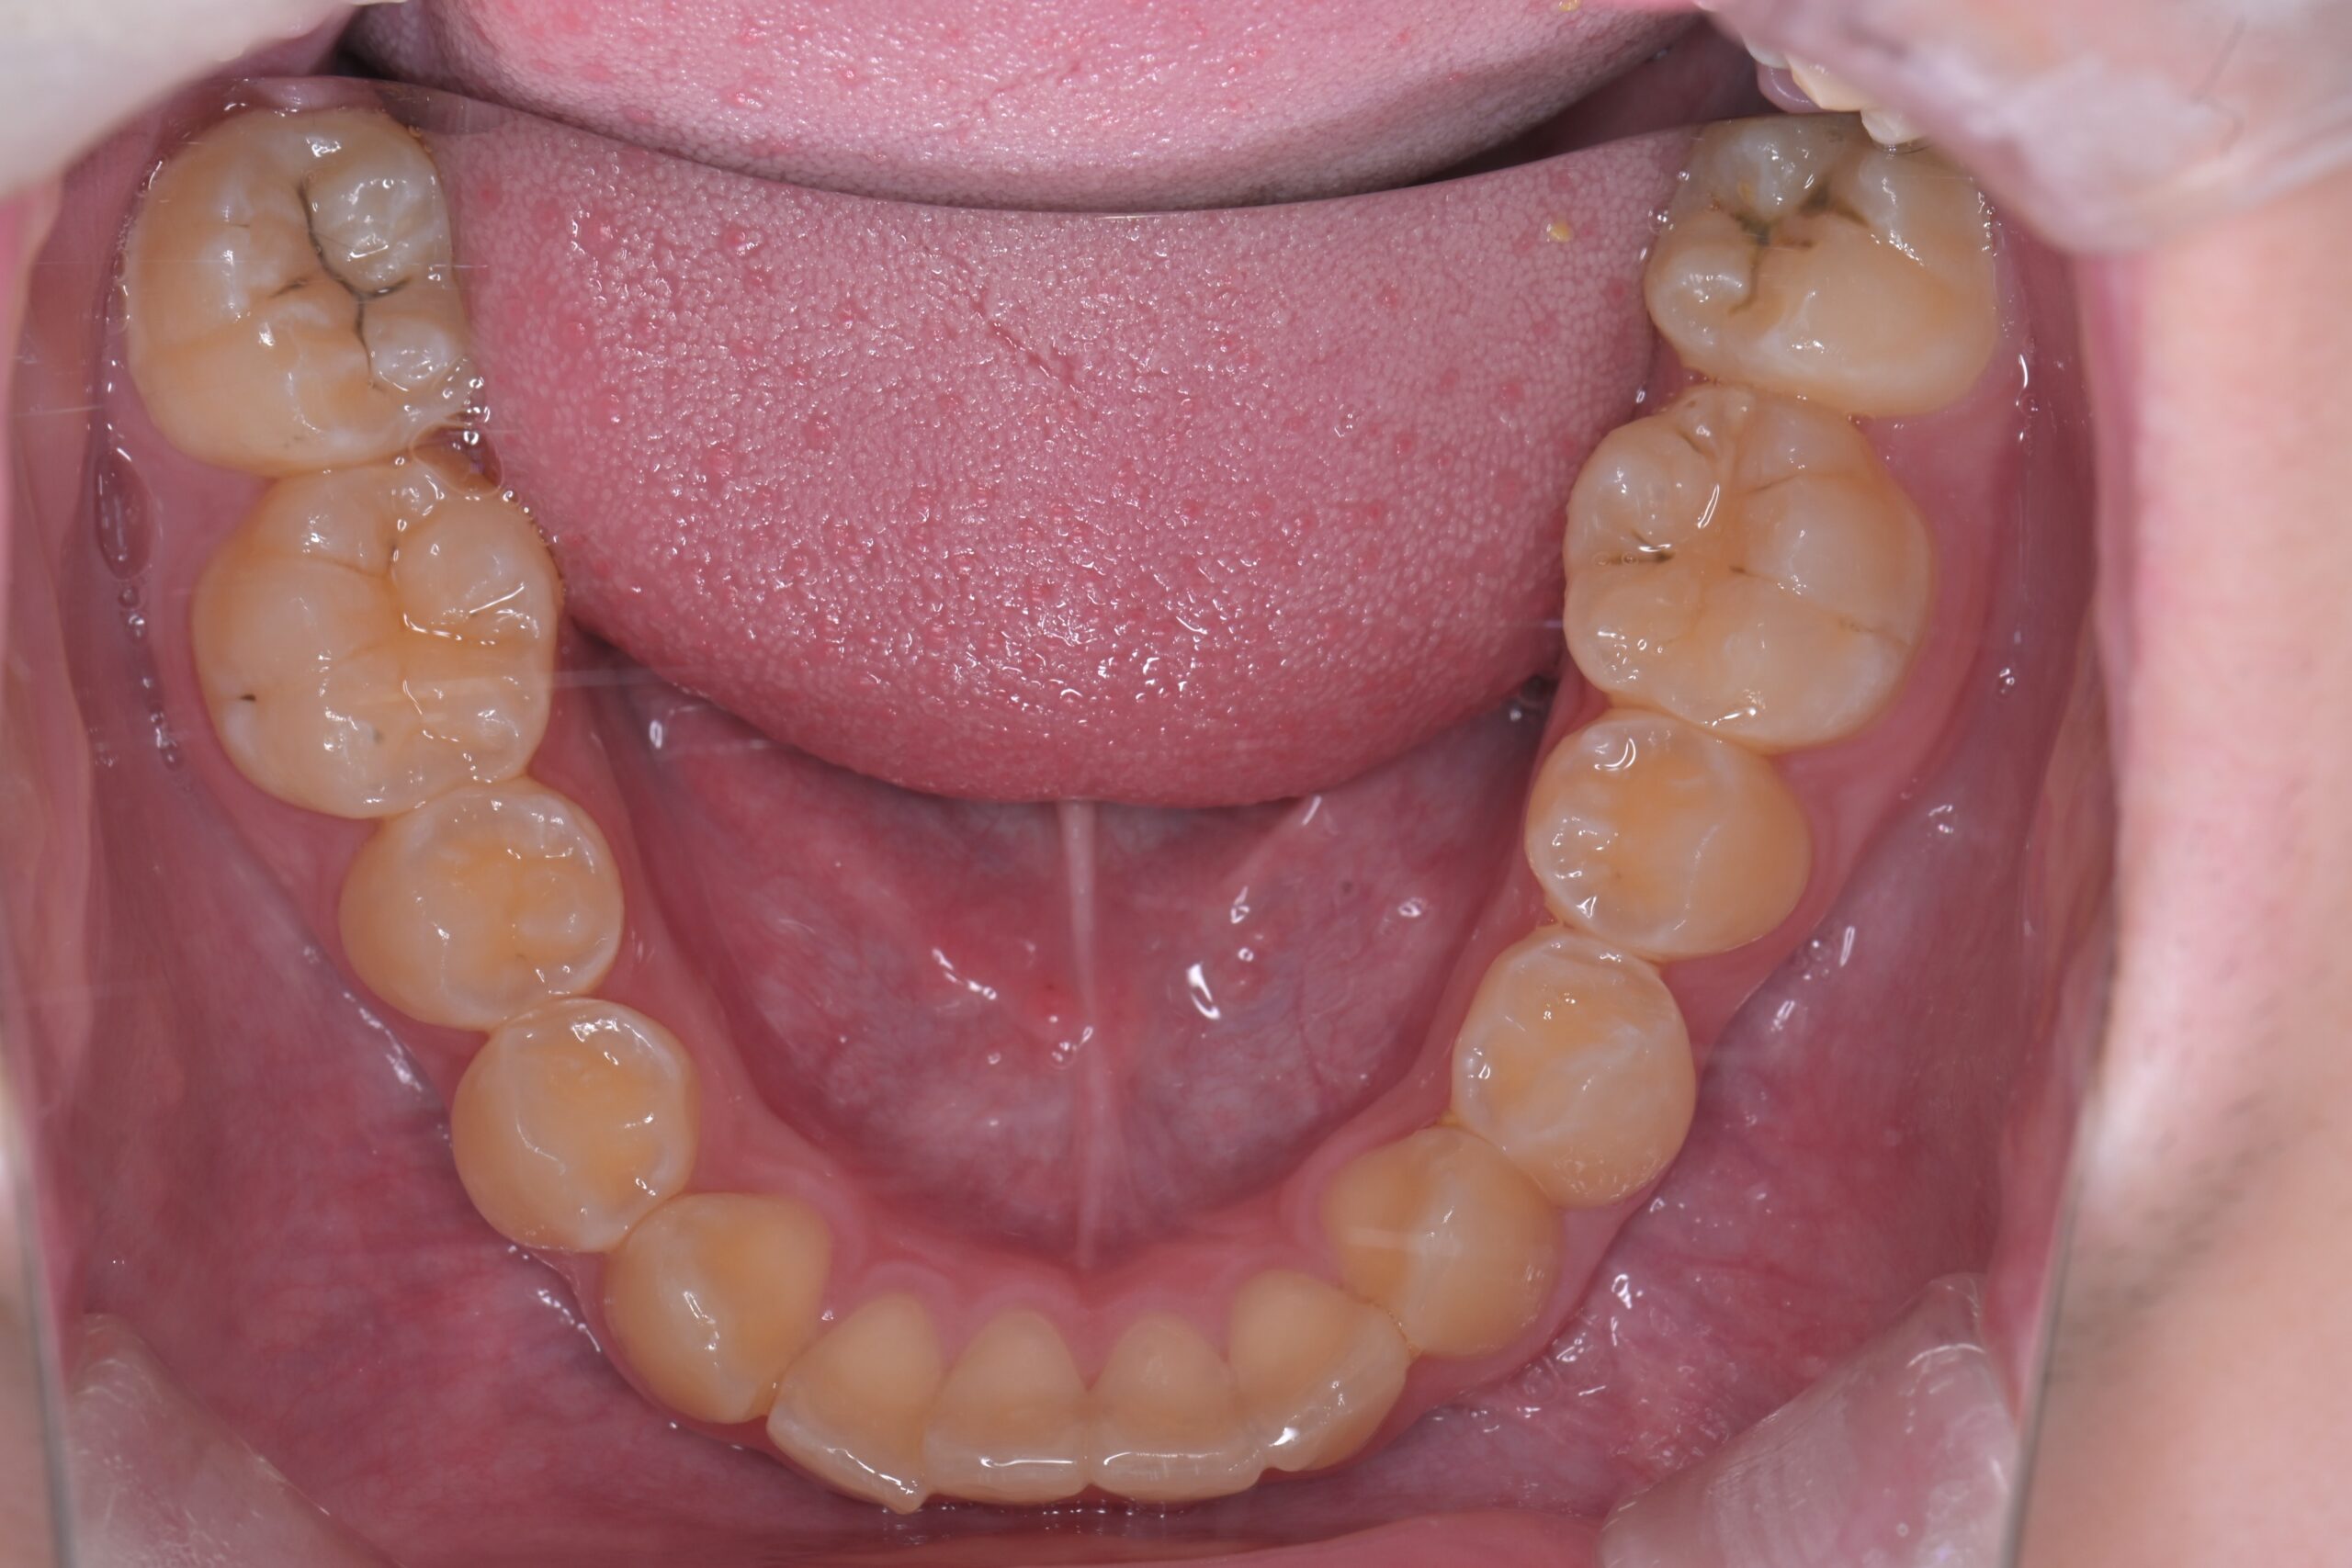

装置除去(下顎)